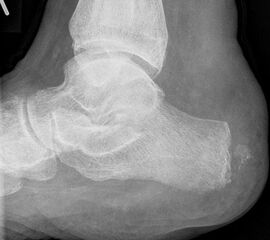

Kalkaneusteilamputationen, Kalkaneusresektion

Indikationen

• Weichteildefekte, die weder konservativ noch plastisch-chirurgisch zu decken sind,

• Lokale Osteomyelitiden mit Knochennekrose und Weichteilbeteiligung (Abb. 50).

Das Ausmaß der Knochenresektion ergibt sich aus der Defektgröße bzw. aus der Ausdehnung der Osteomyelitis 3 (Abb. 52). Eine totale Kalkanektomie ist problematisch, weil danach die Leitungsbahnen unmittelbar dem Körpergewicht ausgesetzt sind.